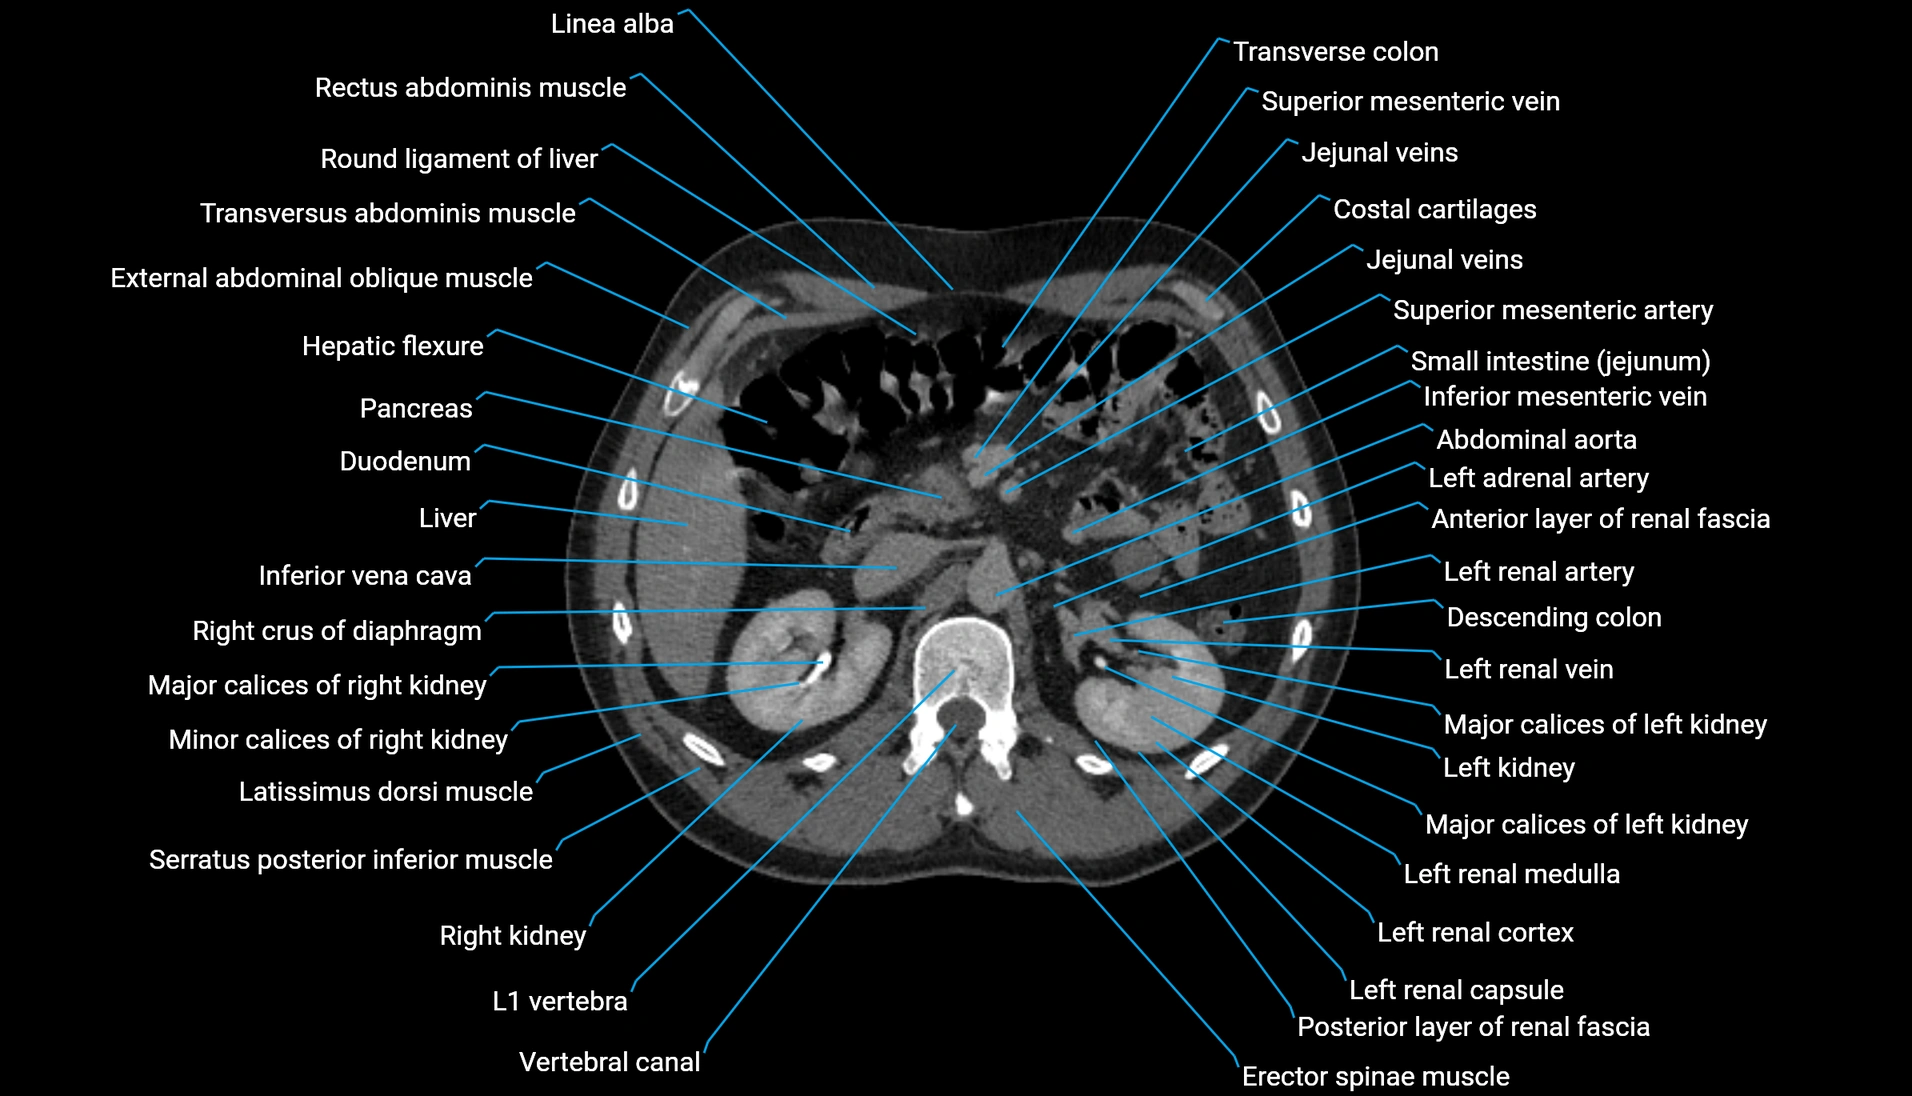

CT Appearance

Non-contrast CT:

-

Demonstrates cortical bone of acetabular rim in excellent detail

Detects fractures, dysplasia, retroversion, or bony overcoverage (pincer impingement)

3D reconstructions used in preoperative hip surgery planning

CT VRT 3D image

CT image